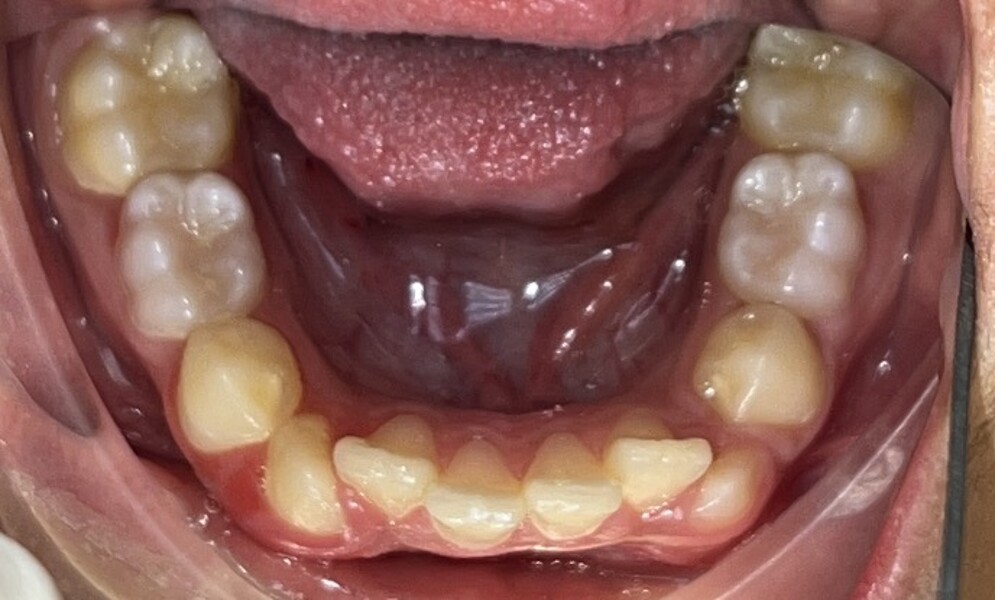

Figs. 2a–e: Pretreatment intra-oral photographs.

Clinical and radiographic evaluation revealed (Figs. 1–3):

a bilateral full-cusp Class II molar relationship;

an increased overjet of 11.7 mm;

a traumatic overbite of 7.2 mm; and

a narrow, collapsed V-shaped maxillary arch with a 2.0 mm midline deviation to the right.